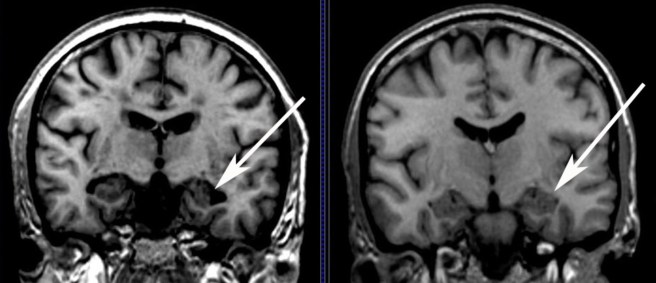

F1.large

A schematic demonstrating the difference between healthy and Alzheimer’s affected brains. Source: MmcNeuro